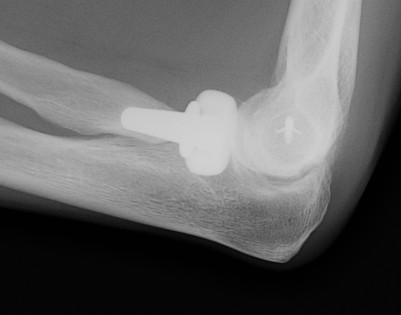

Radial Head Arthroplasty (RHA)

Design

Cobalt chrome / pyrocarbon / titanium

Modular - various head diameter / thickness + various stem sizes + collars to build up radial neck if required

Fixation - press fit v loose fit

Technique Modular Titanium Radial Head Arthroplasty

Lateral approach to elbow / Kaplans or Kocher

- open capsule

- divide annular ligaments

- excise radial head fragments

- use fragments to estimate diameter and thickness of radial head

- if in doubt, downsize

- deliver radial neck

- do not place Hohman retractor anteriorly to protect PIN

- ensure neck cut flat to avoid maltracking

- want 60% contact of radial neck with prosthesis

- insert trial broaches into neck

- insert trial head diameter and neck length

- check no overstuffing on xray

- insert prosthesis

- repair annular ligament

- inspect +/- repair LCL

Results

- systematic review of radial head arthroplasty

- 30 articles with 727 patients

- 8% revision rate

- Mayo Elbow Performance Score: 85% good or excellent

- no evidence of superiority of bipolar / monopolar / fixation technique

- systematic review of minimum 8 year outcomes of RHA

- 10 studies with 432 elbows

- 86% minimal or no pain

- 9% loosening

- 27% degenerative change

- 3% RHA revision rate

- 15% removal of implants